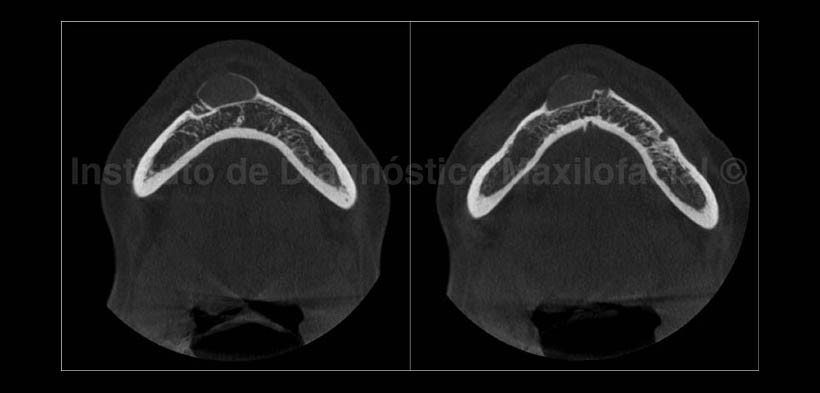

En los cortes axiales (Fig. 4) se observa el defecto óseo en la zona anterior mandibular en donde se aloja el implante, también se evidencia que el implante ha sido recubierto por el periostio mostrándose como una delgada cortical ósea que continua a la tabla vestibular.